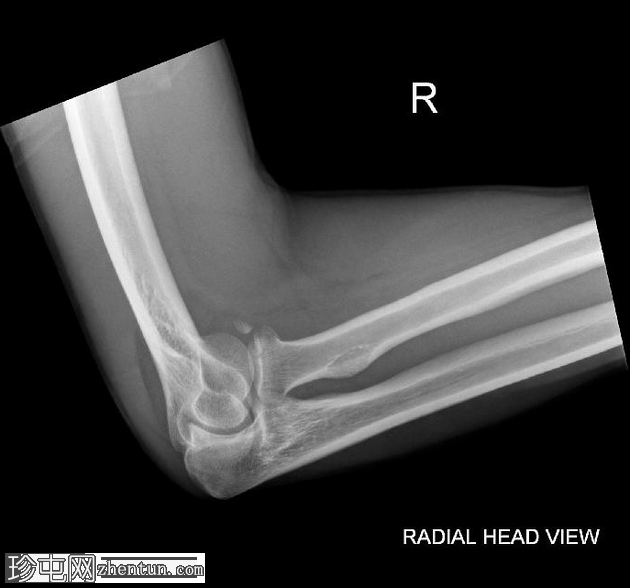

2.png

侧位片

桡骨头关节内粉碎性骨折,关节面轻微凹陷。肱骨远端前侧可见移位的骨碎片,桡骨头位片上清晰可见。可见前后脂肪垫征,提示肘关节积液。

未见肘关节脱位,肱桡骨小头排列保持正常。冠突水平可见复合阴影,可能与软组织重叠或投影伪影有关。桡骨和尺骨骨干外观完整,无骨折征。周围软组织肿胀。